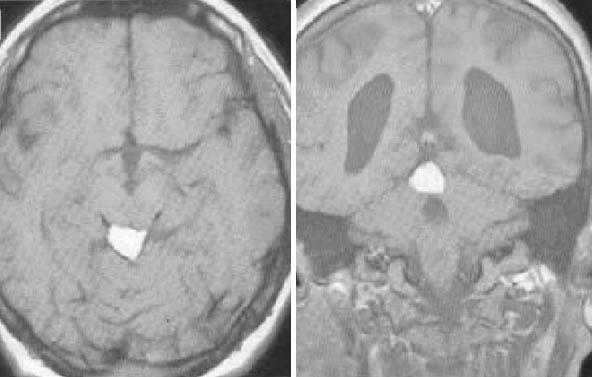

Герминома пинеальной области с метастазированием в хиазмально-селлярную область.

Герминома подкорковых образований слева. Мультикистозного строения опухоль с признаками окклюзии отверстия Монро слева.